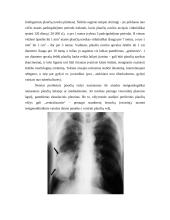

Tomografija, arba pasluoksnis rentgenologinio tyrijo metodas, padeda pamatyti detalų, struktūrinį,...